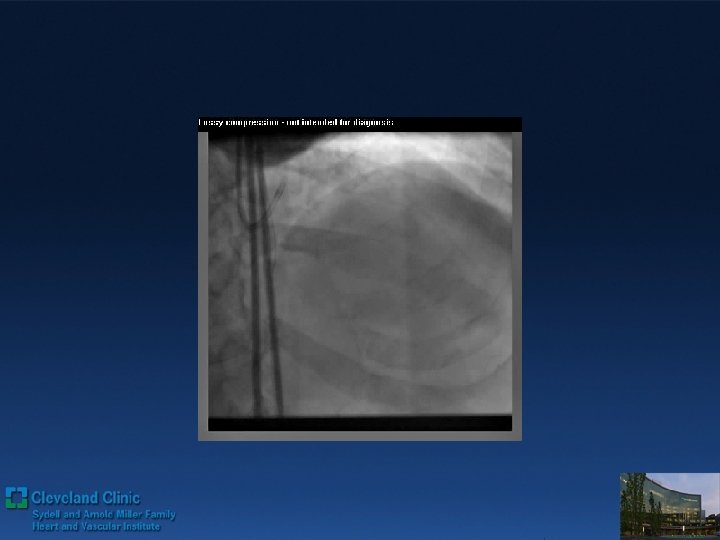

Direct Retrograde Crossing Retro grade wiring with wire trapping inside of ante grade Guide

Direct Retrograde Crossing Retro grade wiring with wire trapping inside of ante grade Guide 3 DES deployed